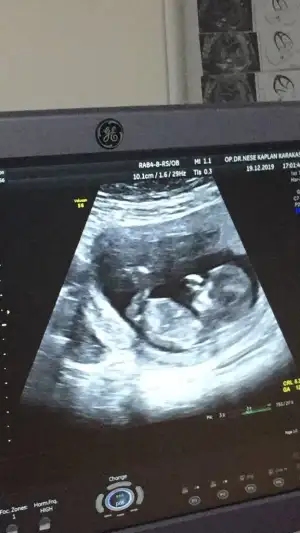

Merhaba bayanlar ben yine doktora gittim ama öğrenemedik cinsiyeti. Bu da son usg. 12h5d

Eklentiler

• IMG_20191221_171735.webp

IMG_20191221_171735.webp

10,7 KB · Görüntüleme: 59